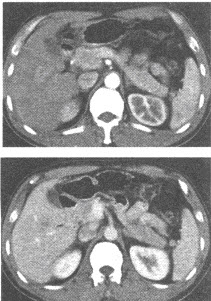

男,41岁。HBsAg(+),AFP45μg/ml。体检超声发现肝右叶有26mm×23mm大小低回声结节。CT增强扫描如图所示。最有可能的诊断为()

A、肝血管瘤

B、肝细胞癌

C、肝炎性假瘤

D、脂肪肝

E、肝腺瘤

B